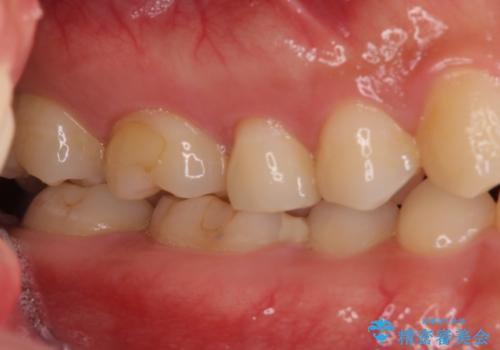

左上奥と右下奥に治療中の歯があり、虫歯を取っている途中で仮詰めの材料が充填されている状態でした。

当初はセラミックインレーによる修復治療を希望されいましたが、カウンセリングの結果、審美性よりも安定性を優先され、PGAインレー(ゴールドインレー・白金加金合金インレー)による治療を行うこととしました。